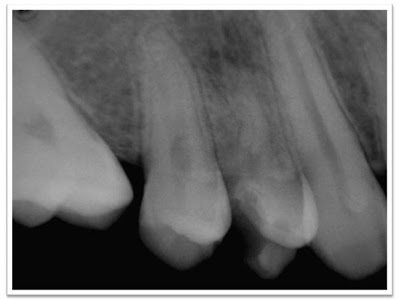

SEGUNDO PREMOLAR INFERIOR CON UN CONDUCTO Y ¿BIFURCACIÓN EN TERCIO APICAL O CONDUCTO LATERAL AMPLIO?

DIAGNÓSTICO: PULPITISTRATAMIENTO: BIOPULPECTOMÍA

INSTRUMENTAL UTILIZADO: COMBINACIÓN DE PROTAPER MECANIZADO CON INSTRUMENTACIÓN MANUAL

OBTURACIÓN: AH 26 + CONOS DE GUTAPERCHA. TÉCNICA HÍBRIDA CON GUTACONDENSSORS.

| Radiografía pre operatoria Radiogrtafía conductometría |

| Radiografía Post Operatoria |

Bifurcación o Conducto Lateral?